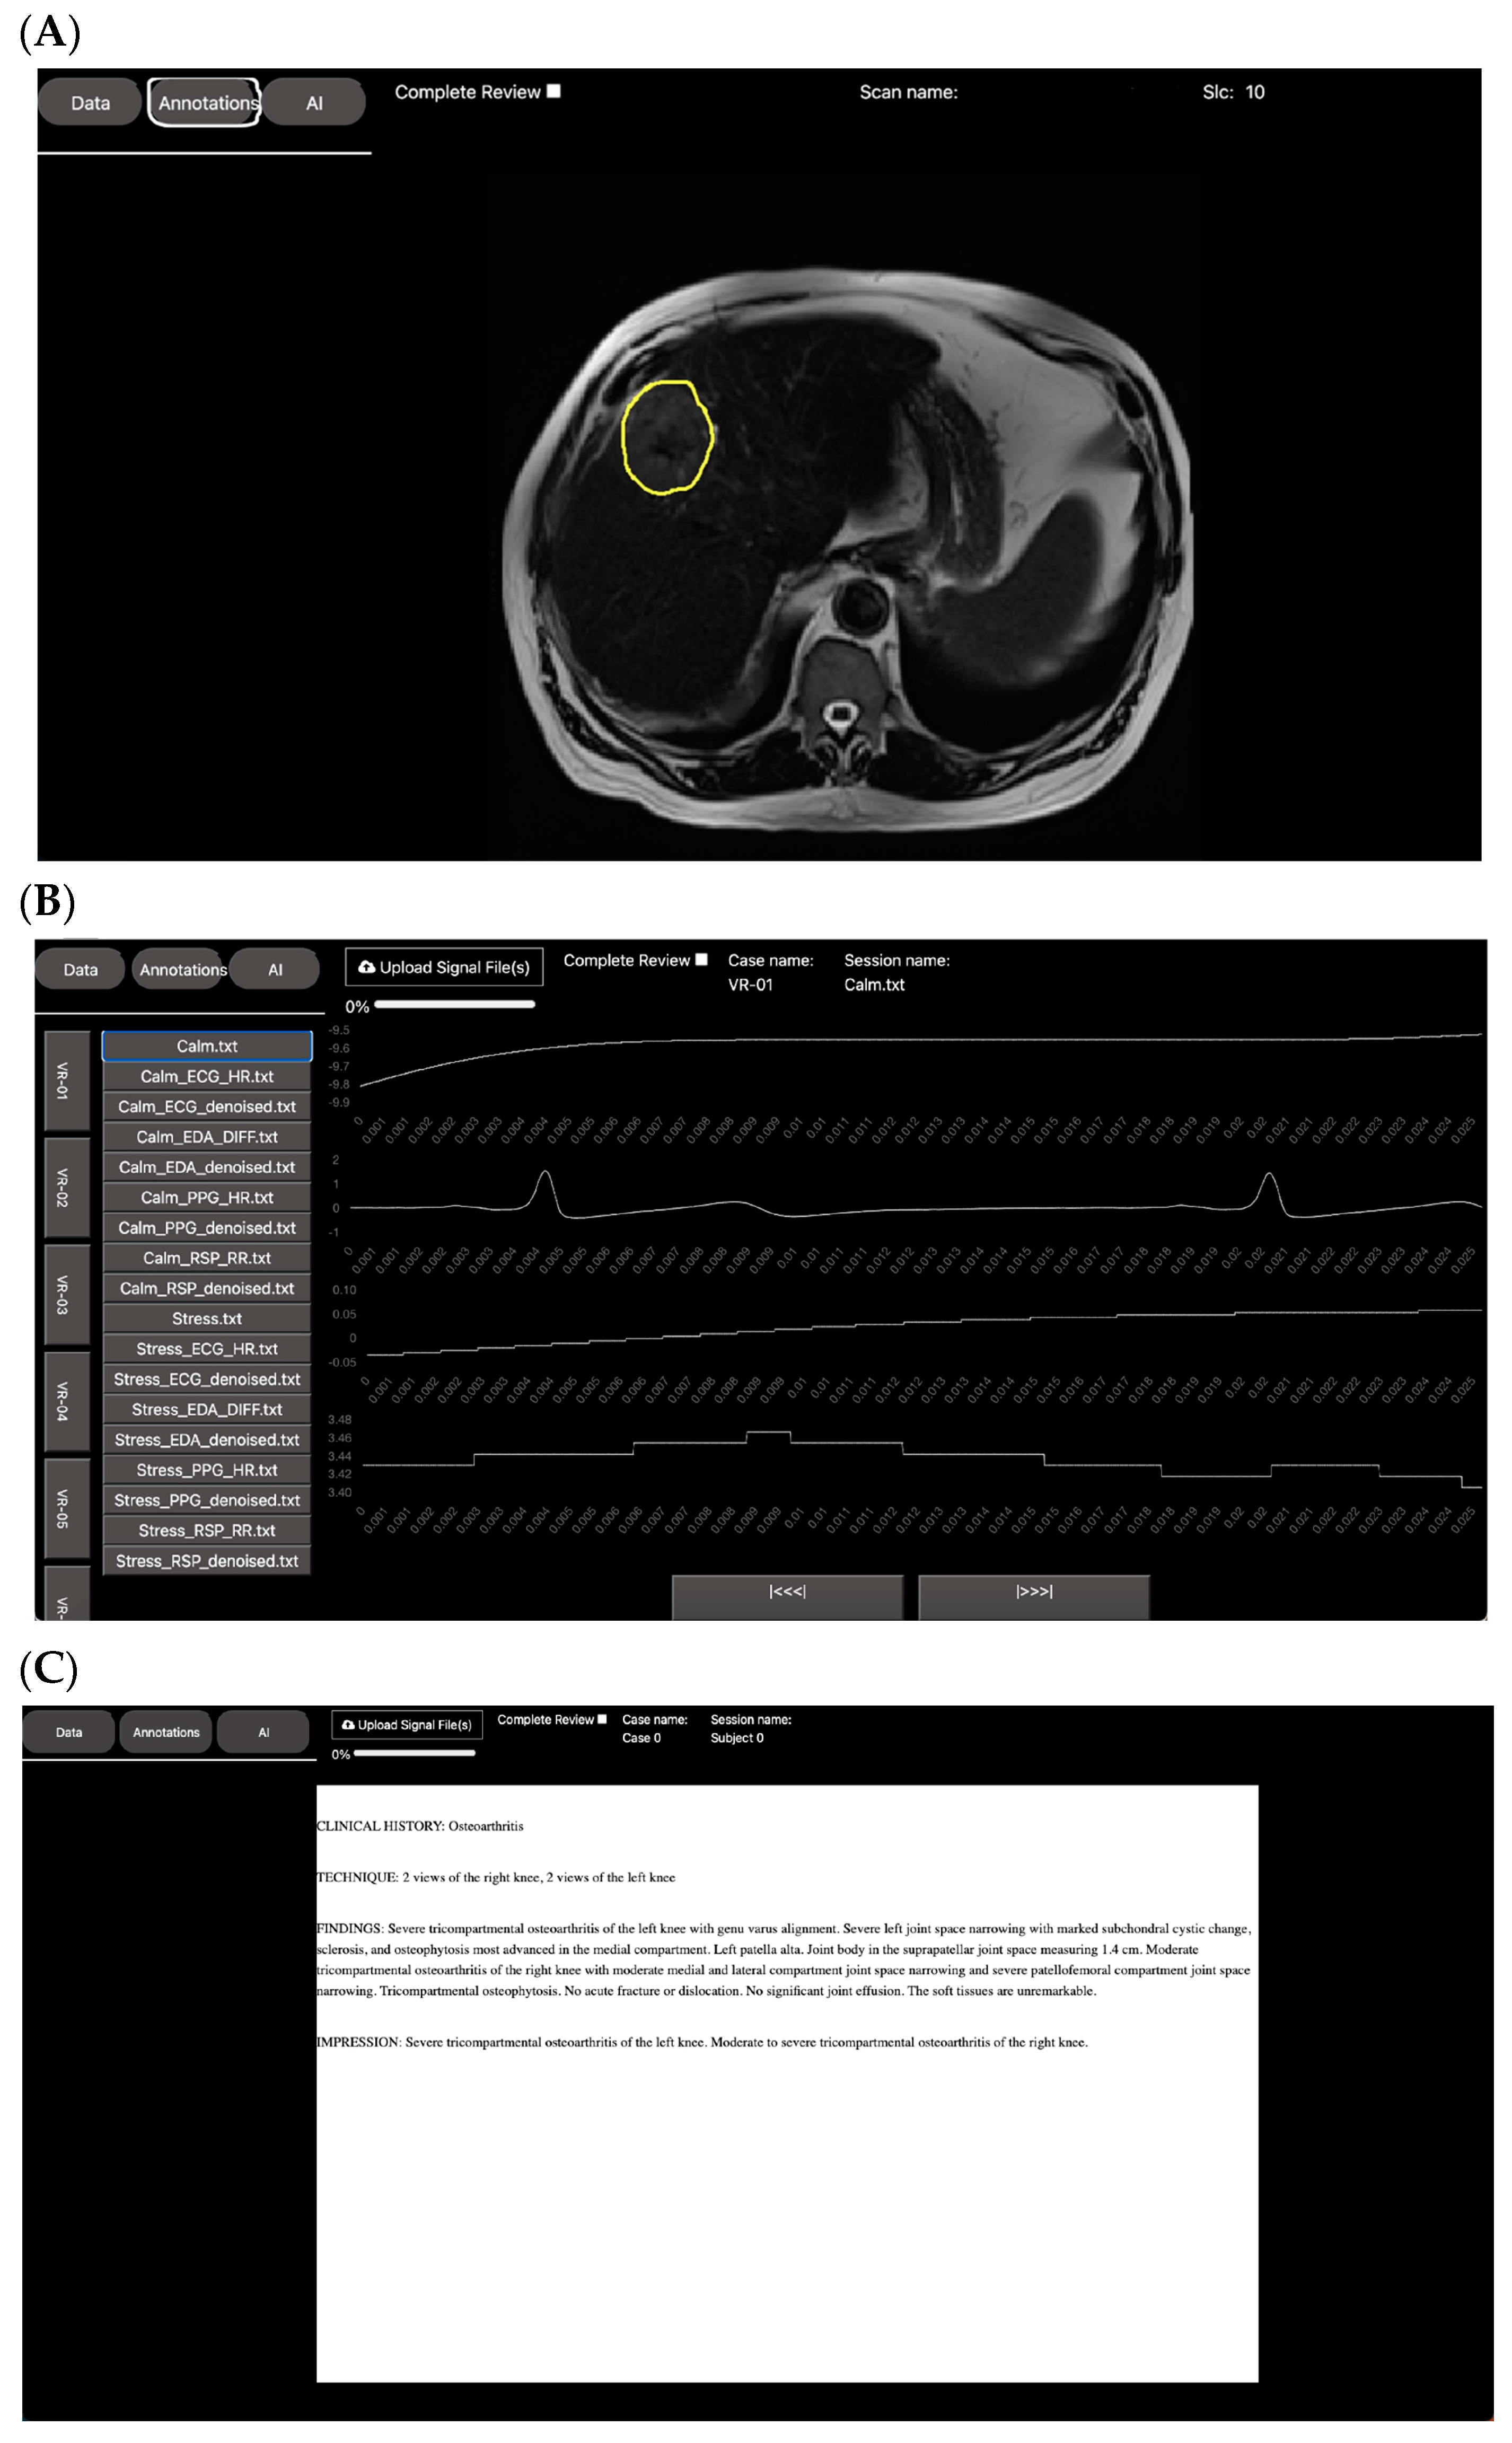

2.1. Leveraging DV for Visualization and Annotation

2.1.1. Spiral VIBE UTE-MRI for Lung Imaging in Post-COVID-19 Patients

2.2. Leveraging DV for Non-AI Expert Model Development

3.1. Web App Design